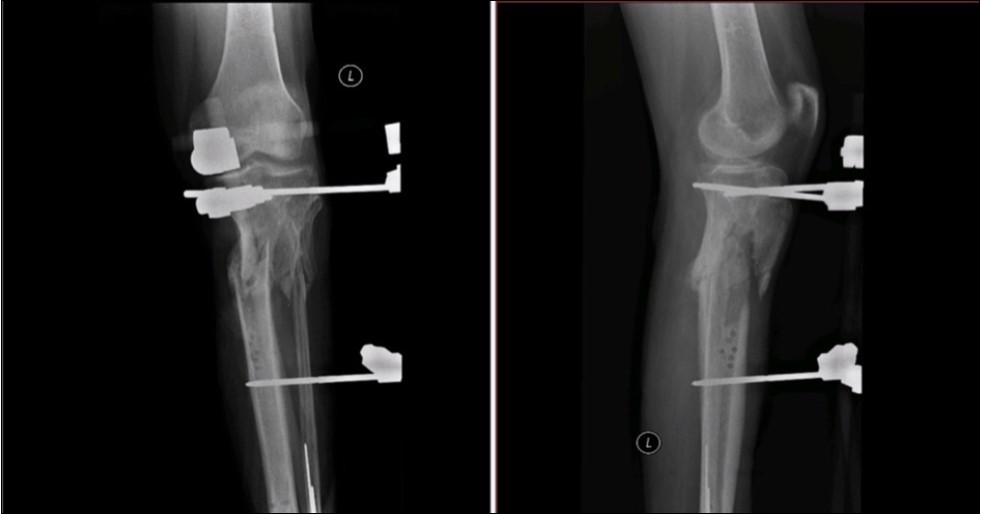

Figure 33. X-ray documentation of the whole treatment of tibia fracture. External fixation was used throughout the treatment until bone was healed. From 9.October 2015 to 2.February 2017